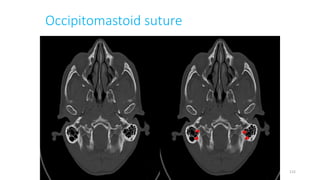

OCCIPITOMASTOID SUTURE

100

115

130

149

171